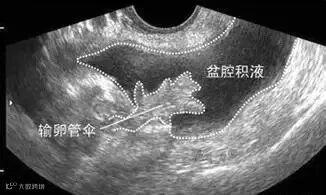

盆腔积液是指对盆腔内液体这一表现的一种描述。可分为生理性盆腔积液和病理性盆腔积液。先来说说生理性盆腔积液。

盆腔处于腹腔最低部,当盆腹腔脏器有少量渗出液、漏出液时,液体会先聚积在盆腔,从而形成盆腔积液。

这里主要指卵巢黄体出血、卵巢囊肿破裂等。就好比盆腔里放着一个充满水的气球,由于特殊的情况气球破裂,里面的水流到了盆腔里。另外,宫外孕破裂会导致大量血液流出,造成盆腔积液现象。